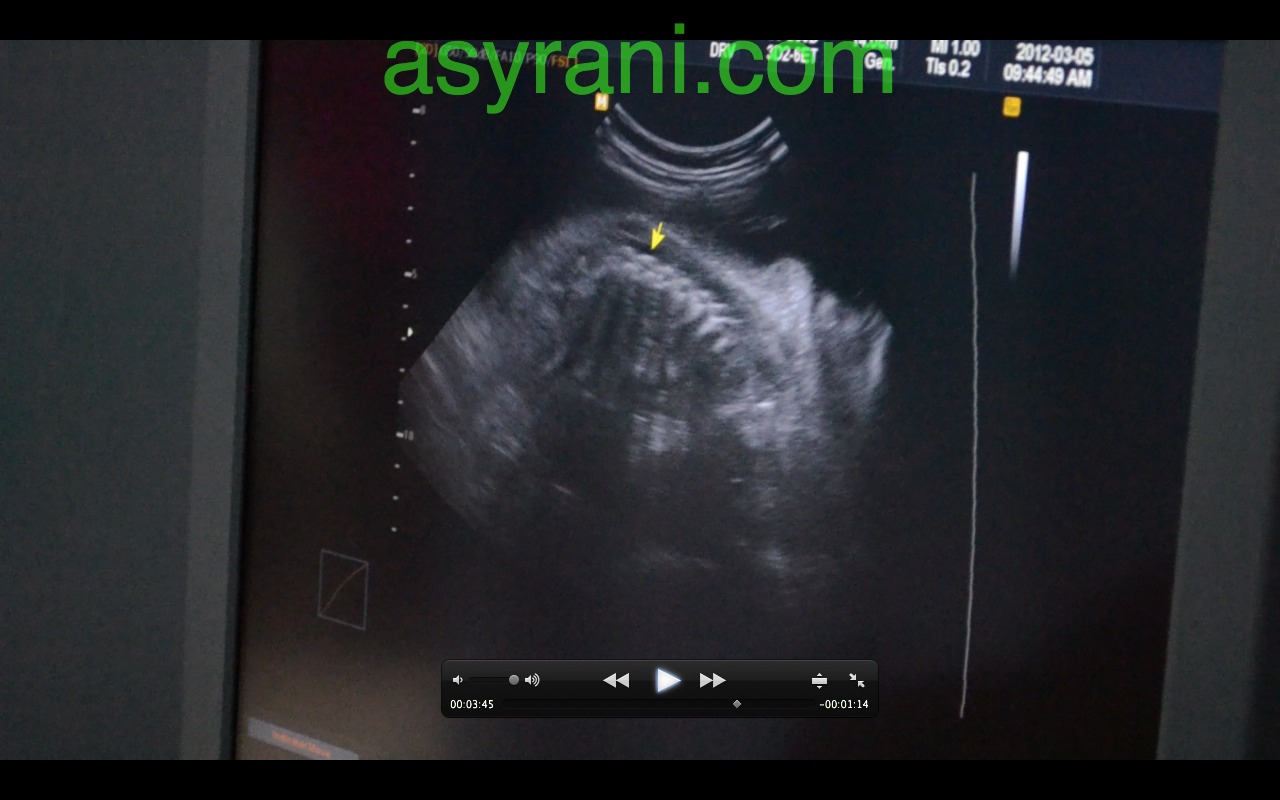

Anak panah menunjukkan Four Chamber jantung baby

Gambar Four Chamber jantung yang lebih jelas